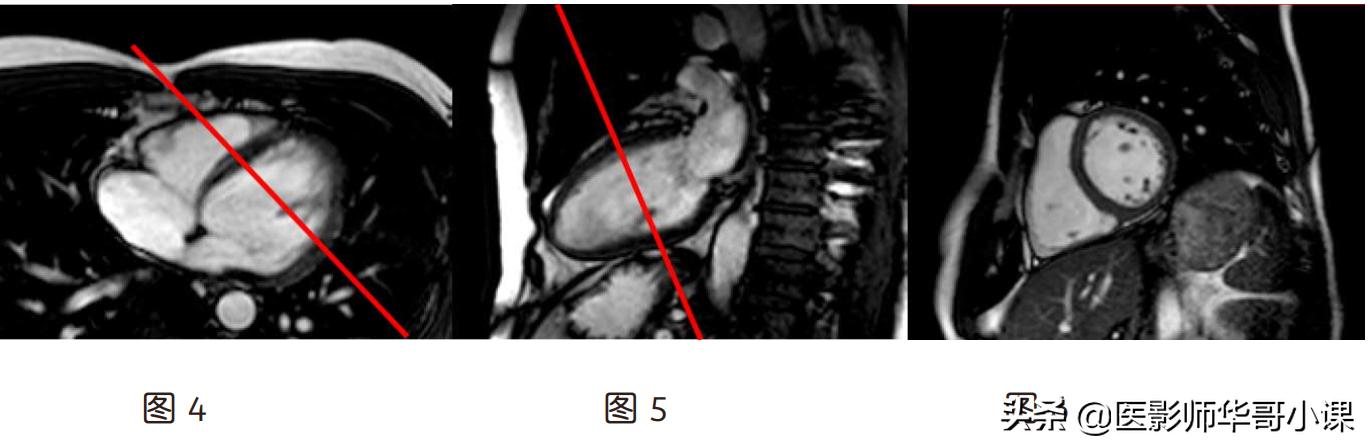

(3)四腔心(图 9):假两腔心上(图 7)定位线平行心尖到二尖瓣中点连线,左室乳头肌

肉层面短轴位(图 8)上平行左室中心到右室口的连线

(4)左两腔(图 12):左室乳头肌层面的短轴位(图 10)上定位线通过左室中心并与室间

隔平行,四腔心上(图 11)平行心尖到二尖瓣口中点的连线